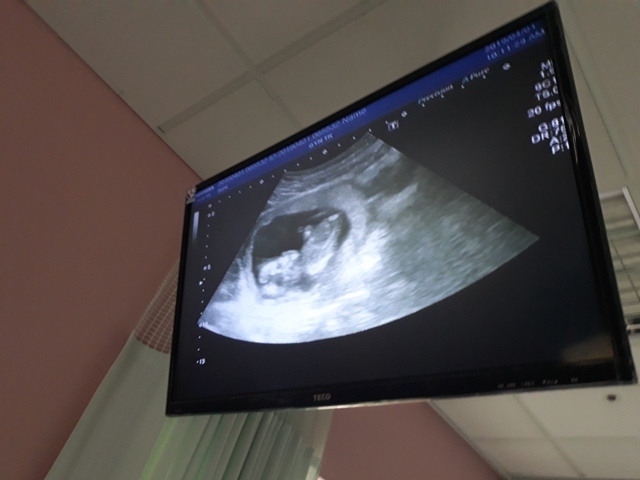

當小純進入診間看診時,我並沒有進去,因為小純說,有時男生不能進去,會被請出來。在外頭等待的我感到很緊張,不久之後,謢理人員請我進入診間,我嚇了一跳,想說發生什麼事了,進入之後,得知小純真的懷孕了,而且已懷了九星期又五天。看診的醫師說,驗孕棒第二條線淡淡的,沒想到胚胎照出來那麼大了,說Baby很健康。還說一閃一閃的是他的心跳,有頭、有手、有腳還有臍帶。小純後來說看了內心覺得很感動,才叫我一起進去看。

小純肚子裡的Baby超音波圖↓